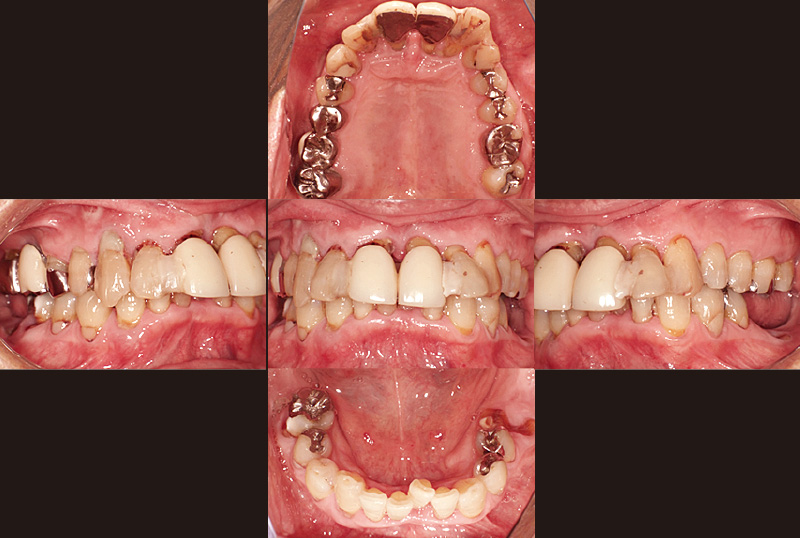

症例の患者さんは、初診時74歳の男性です(図1, 2)。この時は、別の一眼レフカメラで撮影していますが、現在は初診時の5枚法写真は全て歯科衛生士が「ルナビューショット」で撮影しています。一眼レフカメラは女性にとっては少し重たいですし、ミラーを持ちながら片手で撮影するには、ある程度の技術が必要です。また、患者さんにお見せするためパソコンにインポートする際にも一手間が必要です。「ルナビューショット」はとにかく簡単、手軽に撮影でき、「TrinityCore Pro」と連携して、ミラーモードも気にせず自動配置してくれます。オペの様子もアシストする歯科衛生士が随時撮影して、オペ後に患者さんにお見せしながら処置内容を説明しています。

図2 初診時のパノラマX線画像 -